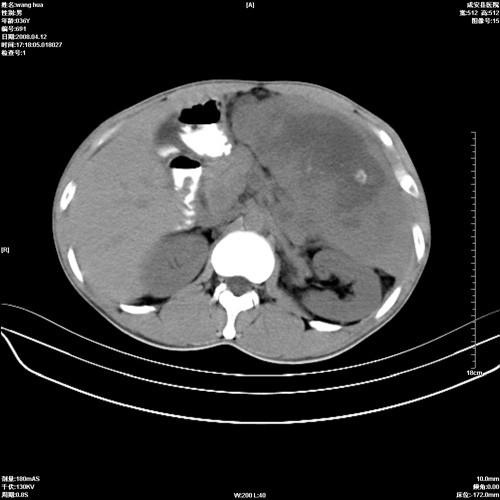

标题: CT12809:男36岁,自感上腹胀5天,B超诊断为脾肾之间占位,血 [打印本页]

标题: CT12809:男36岁,自感上腹胀5天,B超诊断为脾肾之间占位,血

请各位老师先分析一下定位 明天做增强

确实需要强化!先大胆预测一下,来源于脾脏的占位,血管瘤或淋巴瘤可能性大。

脾脏肿瘤,有钙化,增强再说

脾脏病变,密度不均,可见钙化,考虑脾血管瘤,建议增强

脾脏明显增大,其内见巨大低密度灶,境界不清,病史较短,考虑恶性病变脾血管内皮细胞肉瘤可能。建议增强扫描与脾脏淋巴瘤及血管瘤鉴别。